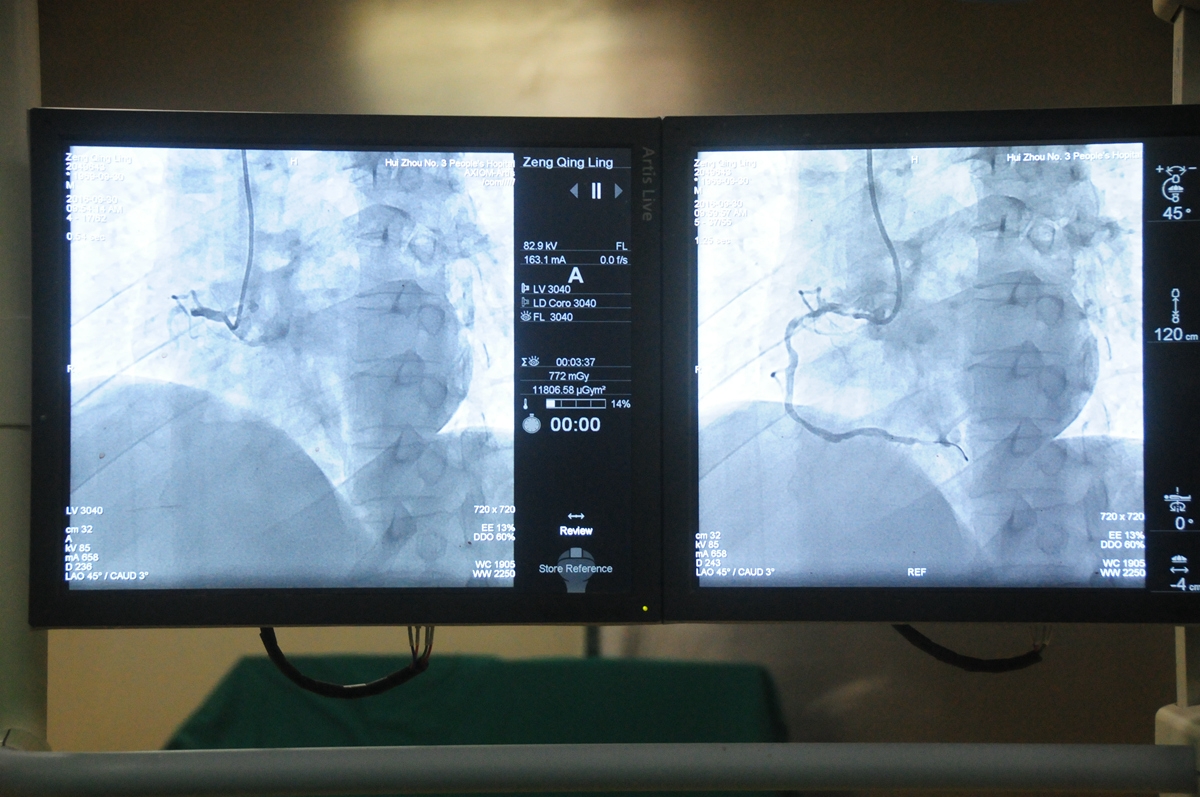

李先生從進(jìn)入導(dǎo)管室到球囊擴(kuò)張時(shí)間僅花了37分鐘,已達(dá)到胸痛中心建設(shè)的基本要求,也再次證實(shí)了“時(shí)間就是生命,時(shí)間就是心肌”。做完手術(shù)后李先生胸悶癥狀即刻緩解,在我院心內(nèi)科CCU(心臟重癥監(jiān)護(hù))病房監(jiān)護(hù)兩天后,病情轉(zhuǎn)危為安,轉(zhuǎn)出了普通病房。

后我院120接到電話后立即趕往楊村,順利將患者接運(yùn)回來直接送至導(dǎo)管室,我院心內(nèi)科住院總立即用最短但通俗易懂的方式告知的手術(shù)的必要性及風(fēng)險(xiǎn)性,患者家屬手術(shù)。曾先生從入導(dǎo)管室門到球囊擴(kuò)張時(shí)間僅花了24分鐘,繞行了急診科并開通綠色通道后,大大縮短了門球時(shí)間。